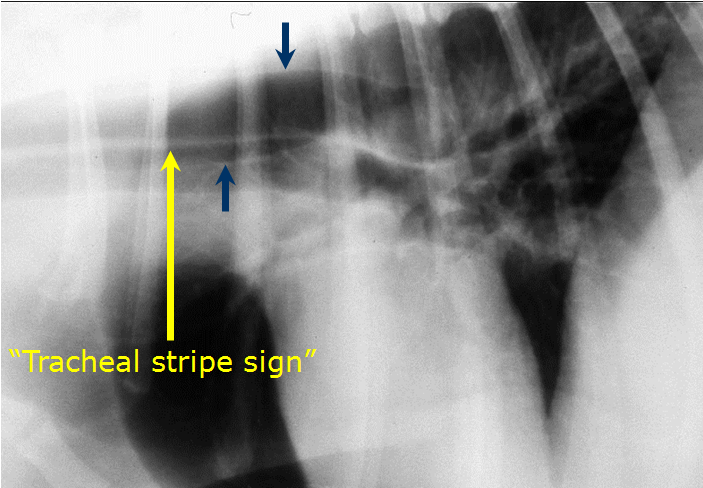

What can be seen here?

Mediastinal mass/fluid

Pleural fluid as lung lobes pushed away from spine

There is a mass here – our mass effect can help – trachea is dorsally elevated and compressed, something solid doing this

Pleural fluid and mediastinal mass